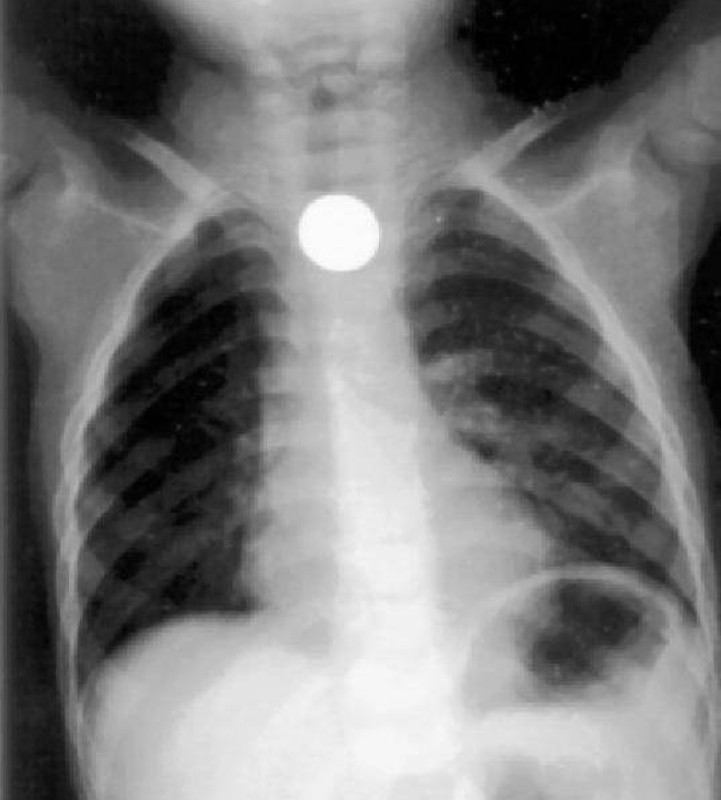

وأوضح رئيس طوارئ مستشفى الأطفال بالمدينة الدكتور فيصل الروقي، أن ابتلاع الأجسام الغريبة يعتبر مشكلة كبيرة، خصوصا في فئة الأطفال من عمر 6 أشهر إلى 3 سنوات، حيث قد تسبب بعض حالات بلع الأجسام الغريبة حالات اختناق ووفاة في بعض الأحيان، مبيناً أن ابتلاعها يعرف بدخول أي جسم غريب لمجرى التنفس أو مجرى الطعام من قِبَل الأطفال من قصد أو من غير قصد، مثل: قطع البلاستيك، قطعة معدنية، بلع بطارية، بلع بالون، الأزرار، الدبابيس، عظام السمك، القطع النقدية.

وأضاف: «تعتمد طرق علاج حالات ابتلاع الأجسام الغريبة عند الأطفال على حالة المصاب، فالتدخل أمر ضروري، ويكون ذلك في بث الطمأنينة للمصاب وإرشاده لإزالة الجسم الغريب مع مراعاة عدم الضغط على البطن، أو إذا فقد المصاب القدرة على الكلام، أو الصراخ، أو فقد الوعي فمن الضروري التدخل الطبي الفوري لمتابعة حالته الصحية وإجراء التصوير الطبي والتدخل الجراحي اللازم إن استدعى الأمر».